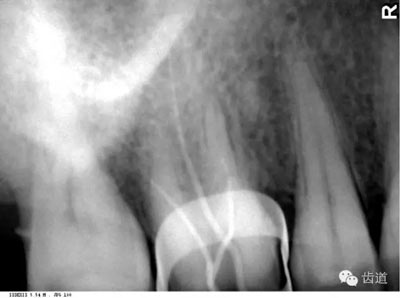

4)外斜線:

由升支前緣下部斜向前下方,為一密度高的帶狀影像。常重疊在第二、三磨牙牙冠處、頸部或根部,使牙髓室或根管不能清晰顯示